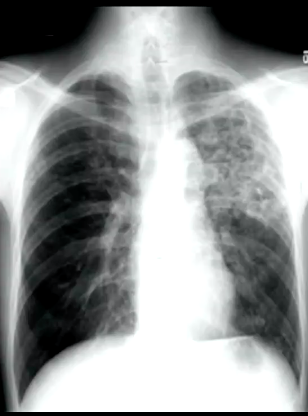

What signs of TB infection are on this CXR?

What type of TB presentation is shown in the CXR?

Miliary TB shown, nodular opacities, with diffuse spread of mycobacterium throughout the lung tissue (this will also be spread diffusely throughout other body tissues).

CT scan will show this even more distinctly.